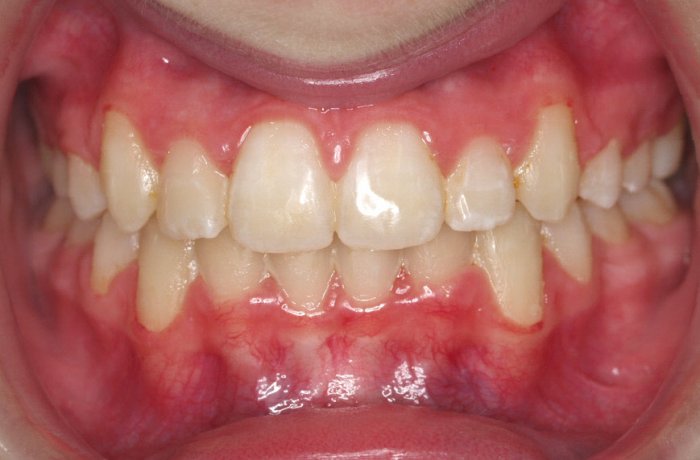

El paciente A.J. de 11 años, acude a nuestra consulta con apiñamiento maxilar importante. El canino lateral (12) está en mordida cruzada. Presenta una Clase II molar y canina, y la línea media está desviada. Se realizó un tratamiento con brackets autoligables metálicos de smartclip 022. La duración del tratamiento fue de 22 meses.

El paciente actualmente ha terminado el tratamiento con brackets y lleva una contención fija de 2-2 en maxilar y 3-3 en mandibular; para complementar también lleva una férula ESSIX durante la noche.